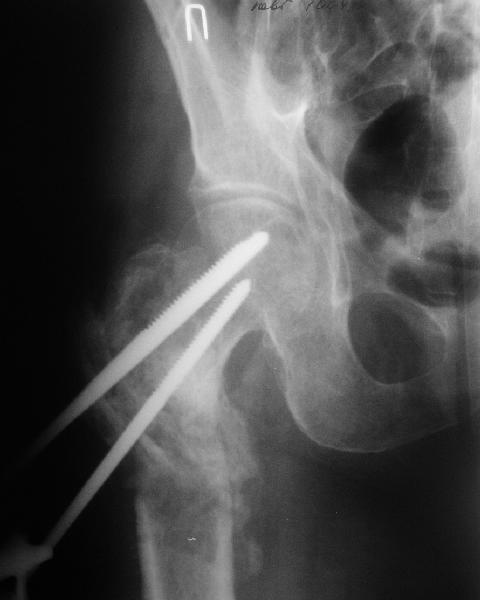

В приложении пример пациента, близкого по картине к тому, что

представил Виктор (варус и смещение периферического отломка на

поперечник кзади). Сделали как раз то, что Виктор исходно намеревался

- аппаратная коррекция и затем гамма.